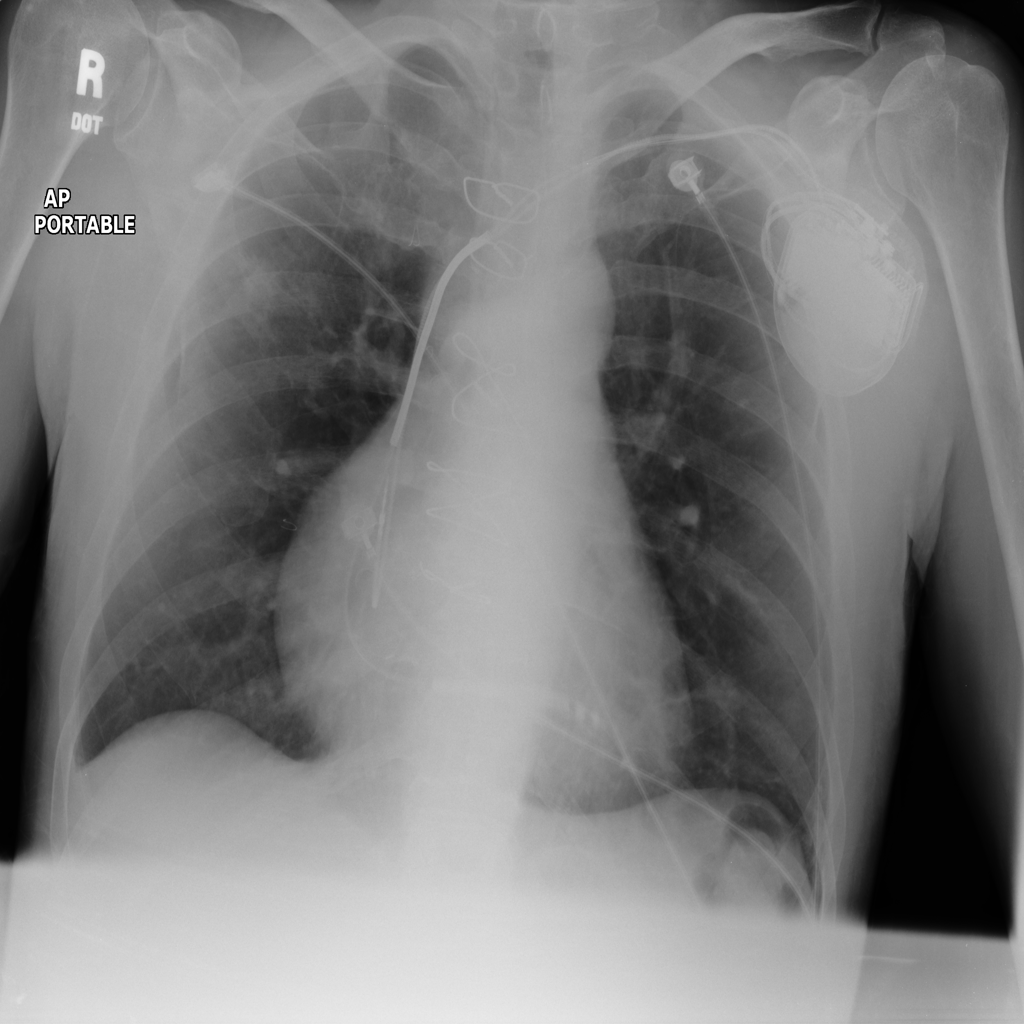

PAT-4639 · IMG-024Mass

PAT-4639 · IMG-024

AP